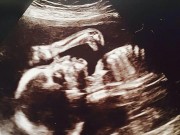

Cặp đôi đang mong chờ một cô con gái sắp chào đời.

Mark thông báo rằng vợ anh lại đang mang thai và lần này, khả năng sảy thai là rất thấp, cả hai rất hy vọng được gặp con gái.

Thậm chí Mark cho rằng, cô con gái đáng yêu từ trong bụng Priscilla Chan đã đưa ngón tay lên với biểu tượng “like” trong ảnh siêu âm để chào bố mẹ, đây là biểu tượng kinh điển của Facebook, mà ai dùng mạng xã hội này cũng biết tới.